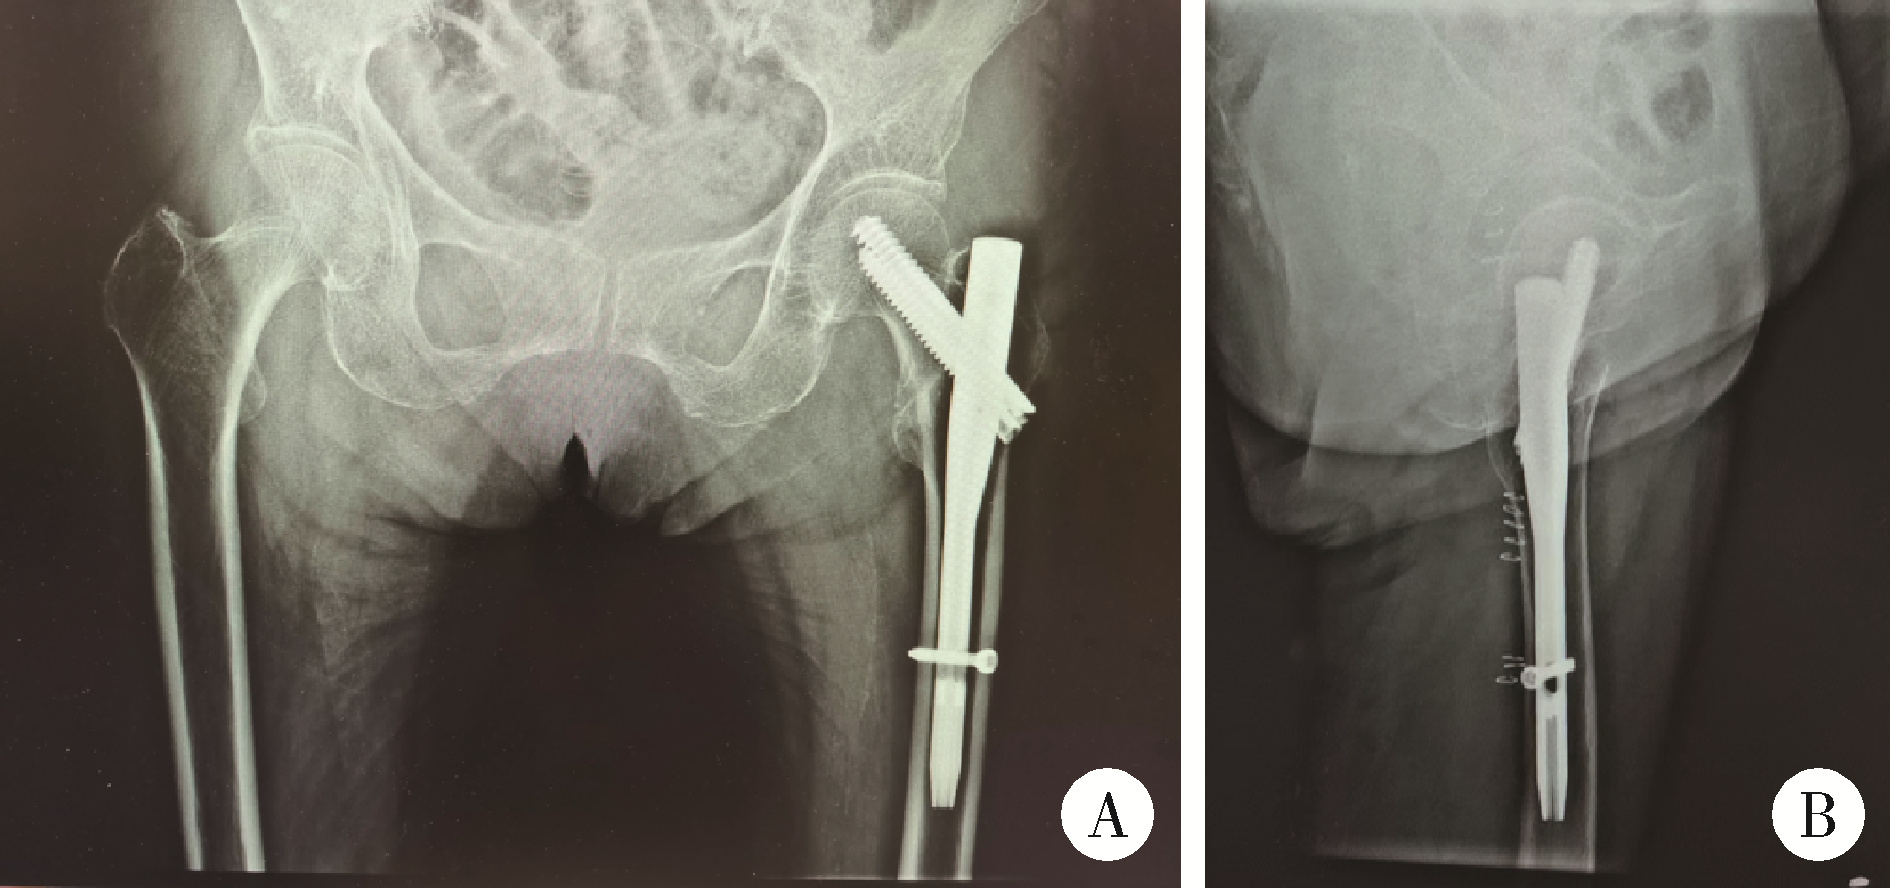

大腿骨近位部骨折:大腿骨頚部・転子部・転子下骨折の手術手技。股骨粗隆间骨折基于CT三柱理论分型方法- 好医术文章- 好医术-赋。Hip Arthroscopic OAT (Mosaic plasty) 股関節鏡視下骨軟骨移植。大腿骨近位部骨折の手術手技に関する専門書。裁断済みスキャン済みのためヨレや小傷はあります業者に裁断してもらいました書き込みはありません価格交渉やまとめ買いはご相談ください。Hip Arthroscopic OAT (Mosaic plasty) 股関節鏡視下骨軟骨移植。- タイトル: 大腿骨近位部骨折 Osteosynthesis & Arthroplasty- 著者: 高平尚伸, 鈴木恵美, 神田善男, 北田貴司- 内容: 大腿骨頚部・転子部・転子下骨折の手術手技に関する専門書- 出版社: メディカ出版- ISBN: 9784840451003ご覧いただきありがとうございます。